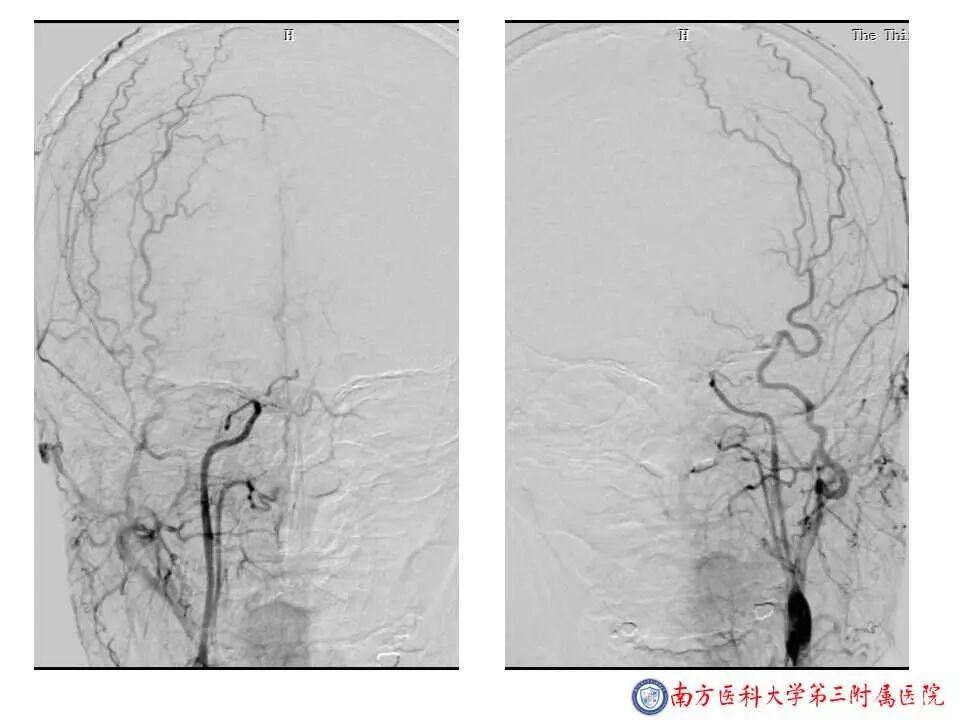

今天为大家分享的是“强生医疗CNV-神经介入专栏”第二十五期,由南方医科大学第三附属医院神经外科主任黄理金教授带来的“Enterprise支架辅助栓塞动脉瘤的优势”精彩讲课视频及PPT,欢迎观看。文章仅代表作者个人观点,如有不同见解,欢迎同道斧正!